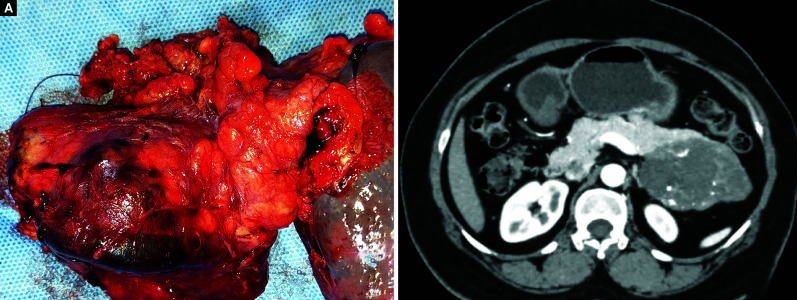

{"title":"Solid Pseudopapillary Neoplasm of the Pancreas: Unraveling Insights from a Single Institutional Study Emphasizing Preoperative Diagnosis of a Rare Tumor.","authors":"Loganathan Jayapal, Santhosh R Kumar, Gilbert Samuel Jebakumar, Siddesh S Tasgaonkar, Sudeepta Kumar Swain, Venkatesh Munikrishnan, Tirupporur Govindaswamy Balachandar","doi":"10.5005/jp-journals-10018-1394","DOIUrl":null,"url":null,"abstract":"<p><strong>Aim: </strong>Solid pseudopapillary neoplasm (SPN), a slow-growing pancreatic tumor with a vague clinical presentation and non-specific radiological features, is rather uncommon. We share our experience emphasizing on preoperative diagnosis and the correlation with final histopathological examination.</p><p><strong>Materials and methods: </strong>This is a retrospective analysis of the 468 patients who underwent pancreas-related surgery at our institution between January 2013 and July 2022. Demographic characteristics, symptoms at presentation, preoperative serum calcium carbohydrate antigen (CA 19-9), lesion characteristics on cross-sectional diagnostic imaging, surgical technique, complications in postoperative period, length of stay, histopathological features, and 3-year follow-up findings of the patients with SPN of pancreas were evaluated.</p><p><strong>Results: </strong>The male-to-female ratio was 1:11 and the mean age at presentation was 33.3 ± 9.5 years. Upper abdomen discomfort was the most common presenting complaint (91%). And five patients had findings suggestive of SPN on preoperative CECT abdomen, and the remaining six individuals were diagnosed solely based on final histological examination. The tumor's median diameter was 5.6 cm (range, 4.1-7.9). The distal body and tail of pancreas was the most common location (63%), followed by the head (36%), and was managed with distal pancreatectomy with or without spleen preservation and Whipple's procedure, respectively. One patient developed grade III Clavien-Dindo complication. The average length of in-hospital stay was 8.27±2.72 days. None of the patients had recurrence on follow-up.</p><p><strong>Conclusion: </strong>Solid pseudopapillary neoplasm of the pancreas is often misdiagnosed preoperatively. Endoscopic ultrasound-guided FNA with IHC will be beneficial to diagnose it preoperatively especially in small-sized tumors with atypical features. Complete surgical resection with adequate margins without routine lymphadenectomy is curative in resectable tumors.</p><p><strong>How to cite this article: </strong>Jayapal L, Kumar SR, Jebakumar GS, <i>et al</i>. Solid Pseudopapillary Neoplasm of the Pancreas: Unraveling Insights from a Single Institutional Study Emphasizing Preoperative Diagnosis of a Rare Tumor. Euroasian J Hepato-Gastroenterol 2023;13(2):50-54.</p>","PeriodicalId":516317,"journal":{"name":"Euroasian journal of hepato-gastroenterology","volume":"13 2","pages":"50-54"},"PeriodicalIF":0.0000,"publicationDate":"2023-07-01","publicationTypes":"Journal Article","fieldsOfStudy":null,"isOpenAccess":false,"openAccessPdf":"https://www.ncbi.nlm.nih.gov/pmc/articles/PMC10785128/pdf/","citationCount":"0","resultStr":null,"platform":"Semanticscholar","paperid":null,"PeriodicalName":"Euroasian journal of hepato-gastroenterology","FirstCategoryId":"1085","ListUrlMain":"https://doi.org/10.5005/jp-journals-10018-1394","RegionNum":0,"RegionCategory":null,"ArticlePicture":[],"TitleCN":null,"AbstractTextCN":null,"PMCID":null,"EPubDate":"","PubModel":"","JCR":"","JCRName":"","Score":null,"Total":0}

Results: The male-to-female ratio was 1:11 and the mean age at presentation was 33.3 ± 9.5 years. Upper abdomen discomfort was the most common presenting complaint (91%). And five patients had findings suggestive of SPN on preoperative CECT abdomen, and the remaining six individuals were diagnosed solely based on final histological examination. The tumor's median diameter was 5.6 cm (range, 4.1-7.9). The distal body and tail of pancreas was the most common location (63%), followed by the head (36%), and was managed with distal pancreatectomy with or without spleen preservation and Whipple's procedure, respectively. One patient developed grade III Clavien-Dindo complication. The average length of in-hospital stay was 8.27±2.72 days. None of the patients had recurrence on follow-up.